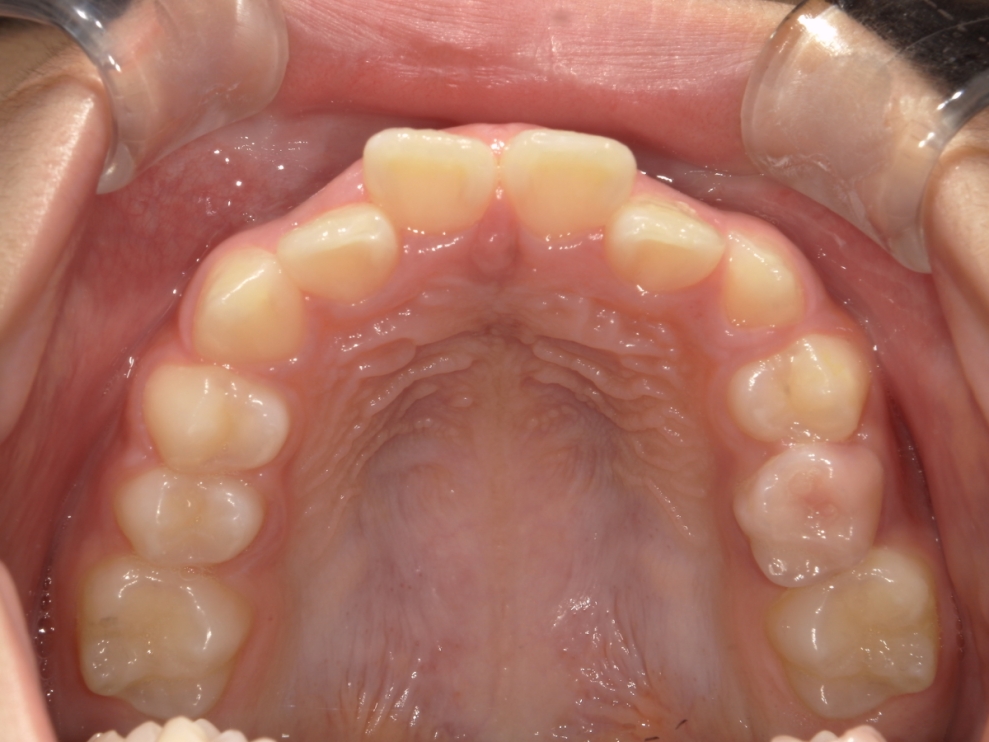

AFTER

治療期間は合計2年9ヶ月で、上下前歯のガタつきは改善し、見た目と機能の両面が整った歯列へと改善しました。

成長期であることを踏まえ、段階的な治療計画を立てました。まずプレオルソを1年1ヶ月使用し、口腔周囲筋や歯列のバランスを整えたうえで、その後、マウスピース矯正インビザライン・ファーストにて矯正治療を行い、さらに1年8ヶ月かけて歯並びを整えています。